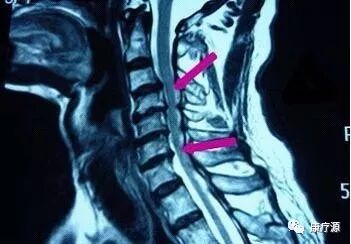

二、脊髓型頸椎?。?/span>

如果在慢性頸部疼痛時(shí)期,放任自流或者沒(méi)有得到科學(xué)的治療,那么患者的疾病就會(huì)發(fā)展,就會(huì)在肌肉無(wú)力的基礎(chǔ)上,發(fā)生韌帶、骨和椎間盤(pán)的退變,患者就會(huì)發(fā)展為頸椎不穩(wěn)、骨質(zhì)增生,產(chǎn)生眩暈、上肢麻木等癥狀。在此時(shí)期,病變累及了椎動(dòng)脈和神經(jīng)根,病情比較嚴(yán)重,治療相對(duì)棘手。病情繼續(xù)發(fā)展,就會(huì)導(dǎo)致骨質(zhì)增生嚴(yán)重,椎管狹窄,壓迫脊髓,使四肢感覺(jué)、運(yùn)動(dòng)和大小便功能受到影響,這就是脊髓型頸椎病。此期累及脊髓,非常危險(xiǎn),稍有外傷,甚至一個(gè)噴嚏都可能導(dǎo)致癱瘓。